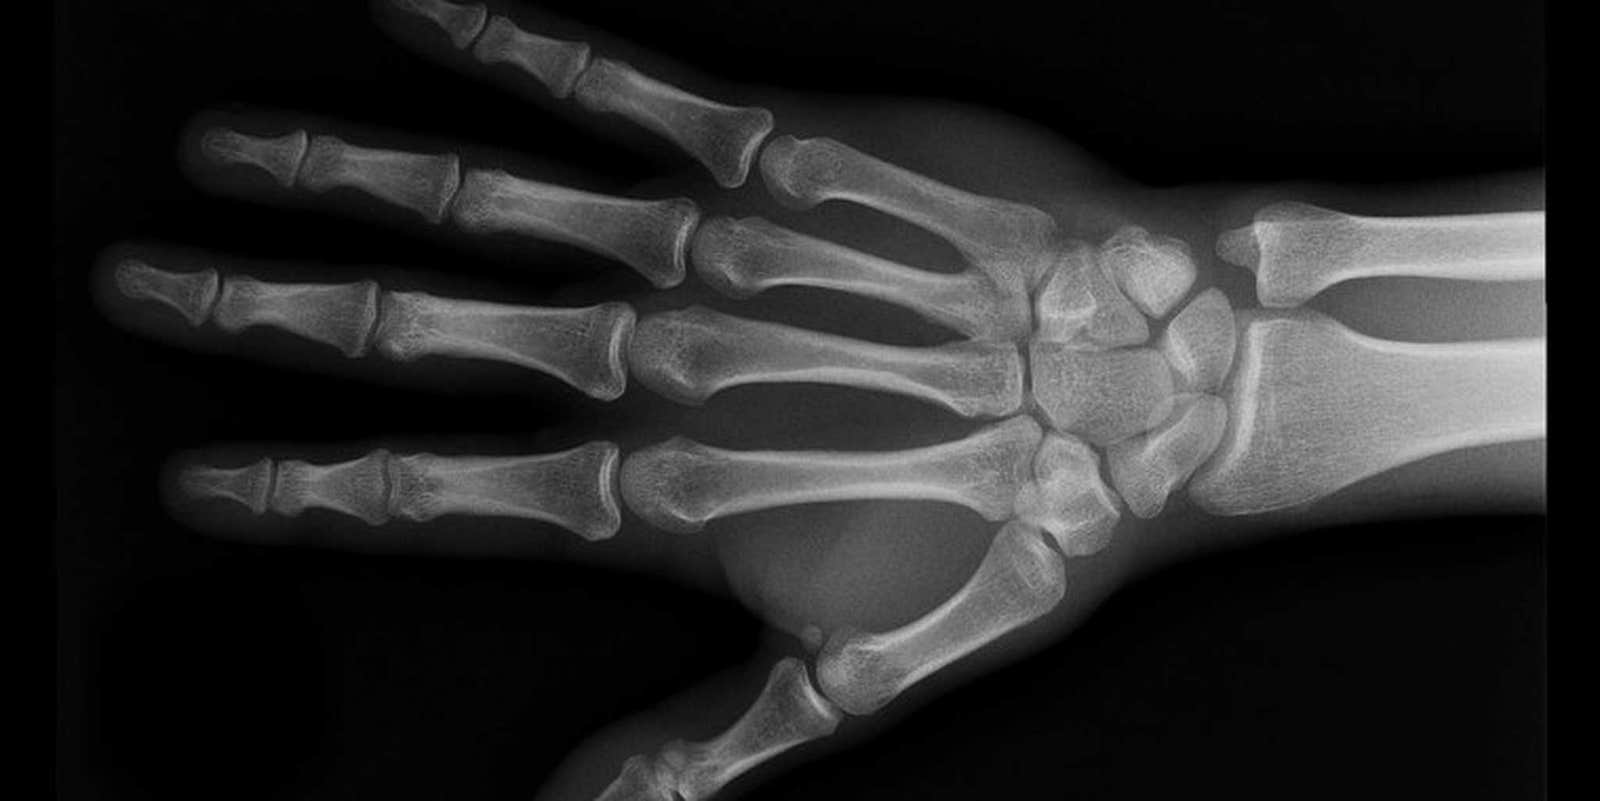

Not everyone has X-ray hardware lying around, so in order to get a beneath-the-skin glimpse of the human body, Drake collaborated with Weiss Orthopaedics of California. He then used Adobe Premiere and Photoshop to turn the video into animated GIFs, and the result is what you see below.

Hand